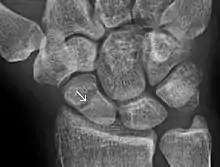

A subtle scaphoid fracture

A more obvious scaphoid fracture on a scaphoid view X ray